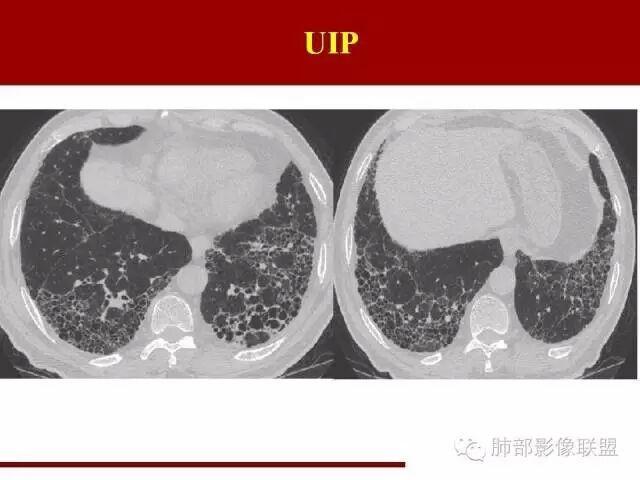

间质性肺炎影像学,间质性肺炎肺纤维化

间质性肺炎ct表现

间质性肺炎ct图片

间质性肺炎早期ct图片

间质性肺炎ct图片特点